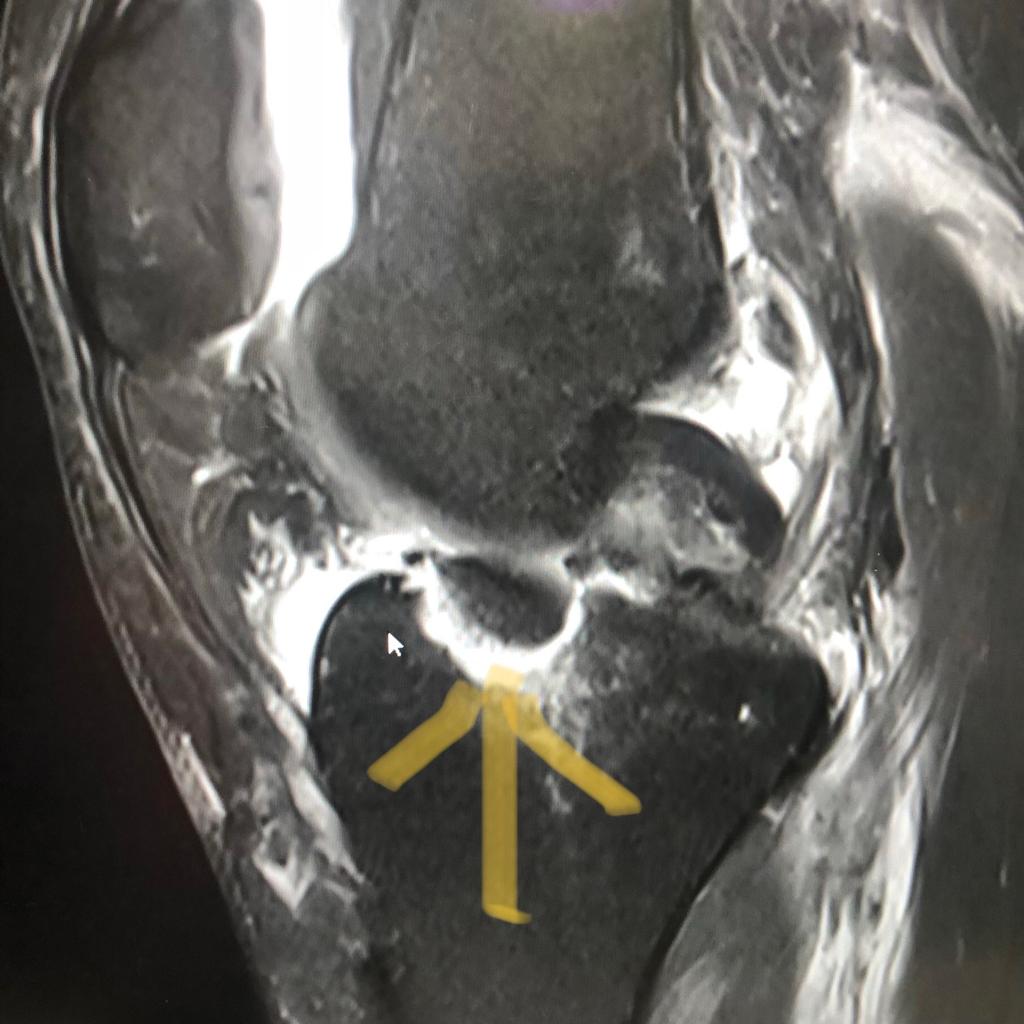

Por @pmpalermo Las holandesas maravillaron a todos en la semana mundialista de Innsbruck. Tras copar el podio de la contrarreloj individual, Anna Van der Breggen protagonizó un auténtico recital en la prueba en línea. Eminence fracture. Can’t believe it. So many emotions now. Will heal, but will take time… (weeks). pic.twitter.com/DFhzDeKw9Y — Annemiek van Vleuten (@AvVleuten)…